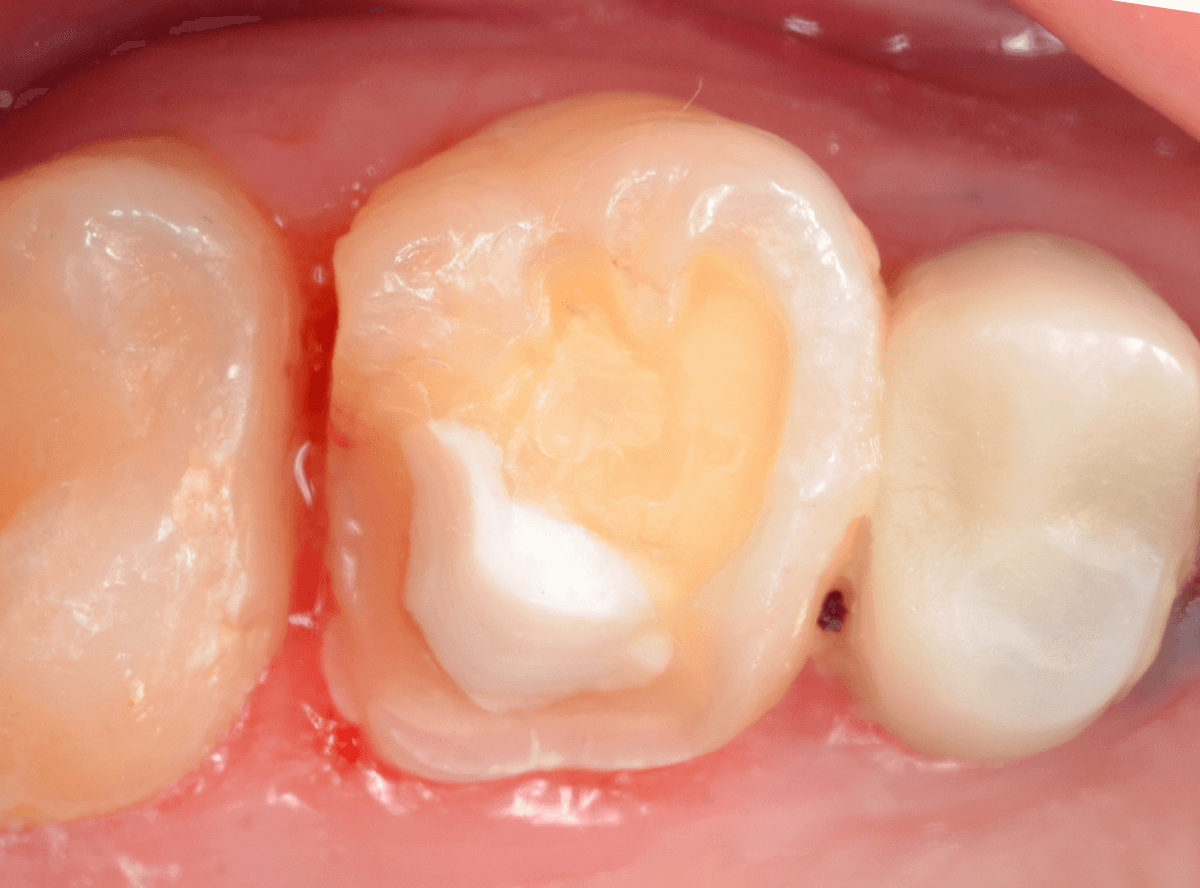

Case.28 虫歯治療後、半年以上来院されなかった患者さん

虫歯を治療して、セメントで歯を削った部分を封鎖した後、再修復を検討中で、半年以上来院されなかった患者さんです。

虫歯を治療して、セメントで封鎖した状態というのは、家でいえば、しっかりした屋根がない状態です。

今回は、セメントの一部がはがれる程度で済んでいましたが、虫歯が再発し、再治療、最終修復物の変更の可能性も出てきます。

治療再開後、セラミックの最終修復を希望されましたので、歯をトリミングし、型取りします。